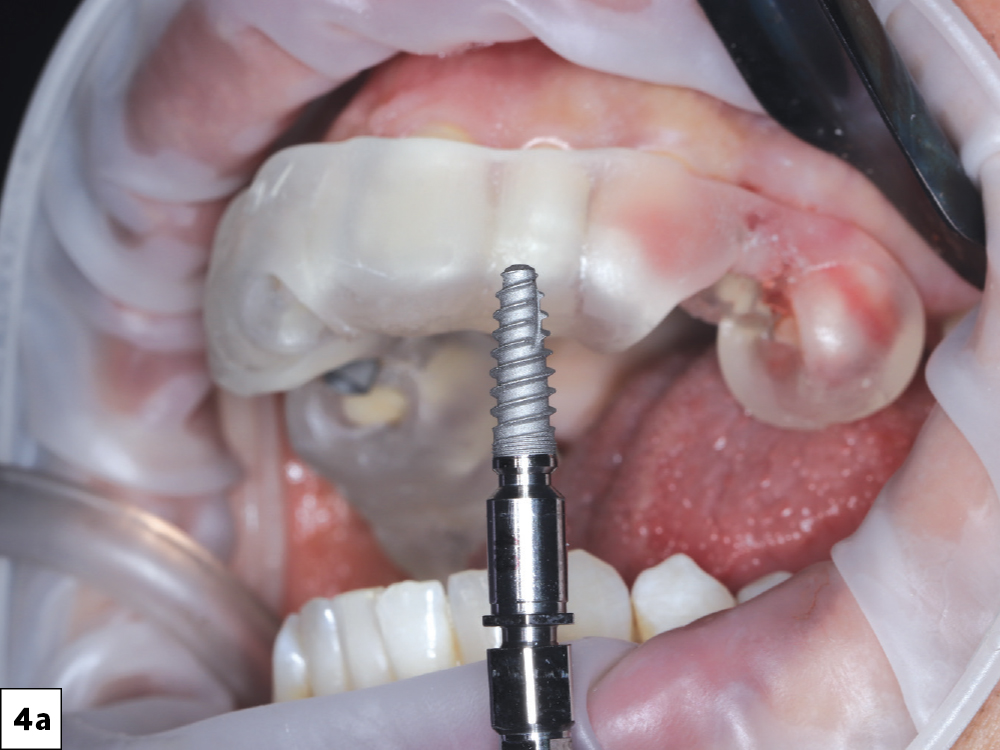

Surgery was performed under local anesthesia with the printed guide securely seated for full control of angulation and depth

Figures 4a–4c: Surgery was performed under local anesthesia with the printed guide securely seated for full control of angulation and depth. Two Glidewell HT™ Implants (Glidewell Direct; Irvine, Calif.) were placed according to the digital plan, achieving excellent primary stability.

Resonance Frequency Analysis (RFA) was used to confirm an Implant Stability Quotient (ISQ) appropriate for immediate loading

Figures 5a–5c: Resonance Frequency Analysis (RFA) was used to confirm an Implant Stability Quotient (ISQ) appropriate for immediate loading.